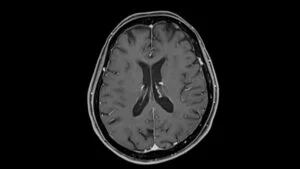

Multiple System Atrophy (MSA) is a rare, rapidly progressive neurodegenerative disease that affects the body’s most vital automatic functions—movement, balance, blood pressure, bladder control, and more. It gradually robs individuals of independence and currently has no cure, no definitive diagnostic test, and only limited treatment options.